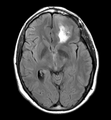

Data